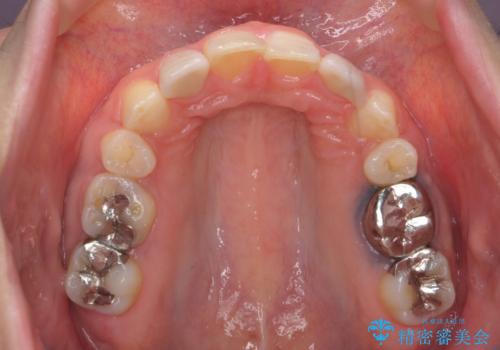

上顎2番は矮小歯だったのをセラミックで被せています。

- 矯正治療85万円 補綴治療16万円(emaxクラウン、仮歯)費用は治療当時の料金となります

口唇の突出感がなくなり、理想的な横顔になりました。

虫歯治療は、他院で保険治療で行なって頂いています。